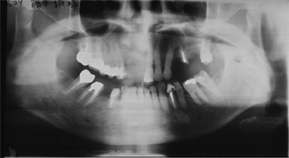

上顎にインプラント治療予定ですが、歯を支える骨も溶けて薄くなってしまっている状態でした。

さらに、神経損傷や麻痺のリスクを回避するため、神経や血管の位置や骨の硬さの値をより正確に把握することが可能なCTで撮影を行います。そのCTデータを3D立体構築画像検査による精密診断を必ず実施ししてから手術を行います。

骨量や歯周組織が吸収、減少してしまっている場合は、骨造成や骨移植及び歯肉移植などの手術を併用します。当医院で使用する人工骨は牛から取り出した成分を加工して作られた人工骨とリン酸カルシウムを材料として作られた人工骨です。いずれも長期に応用されているもので不具合は報告されていません。